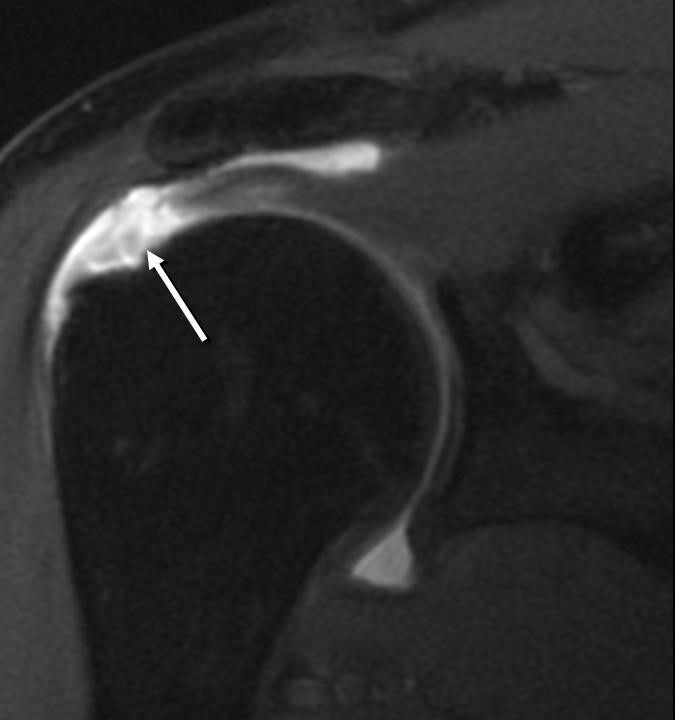

Hình ảnh điển hình tổn thương GCX

Hình 4. Hình ảnh tổn thương gân cơ trên gai